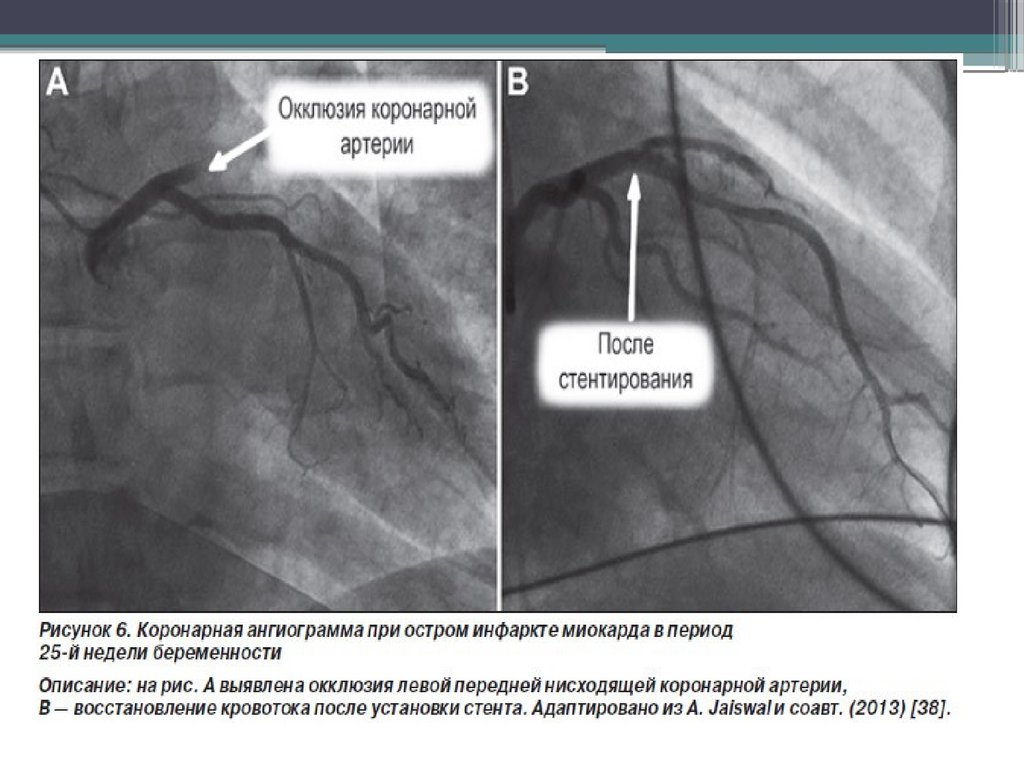

Спонтанная дессекция интимы КА у беременных